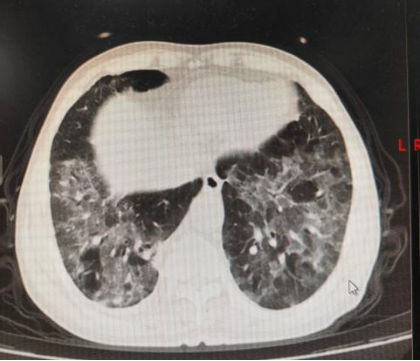

胸部CT平扫(2025.10.17):双肺多发模糊斑片影。右肺上叶点状致密影。

双肺炎症,双侧少量胸腔积液;

右肺上叶钙化灶,右肺水平裂小结节。